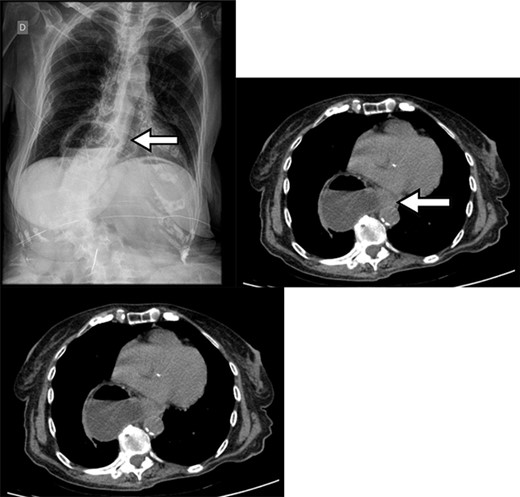

Upon initial physical examination, the patient presented regular general condition with stable vital signs, flaccid abdomen without peritonitis signs, masses or visceromegaly. The rectal examination contained hard stools and no signs of bleeding. Due to the clinical presentation suggestive of upper gastrointestinal tract obstruction, laboratory tests were requested, which showed abnormal renal function (KDIGO 2). The abdominal radiography in three views showed air-fluid levels located in the epigastric region, corresponding to the distended stomach (Fig. 1). Abdominal tomography showed gastric hernia containing the antropyloric junction, which was located above the gastroesophageal junction, therefore, mesenteroaxial gastric volvulus.

Chest X-ray with gas distension and the air-fluid level above the diaphragmatic domes and contrast-enhanced abdominal CT showing gastric volvulus in hiatal hernia.